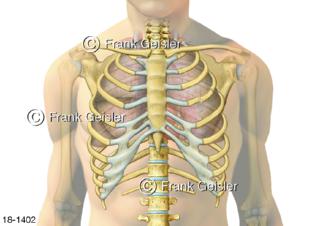

18-1402 Notfall doppelter Rippenbruch Rippenfraktur, schmerzhafter Bruch oder Riss der Rippen